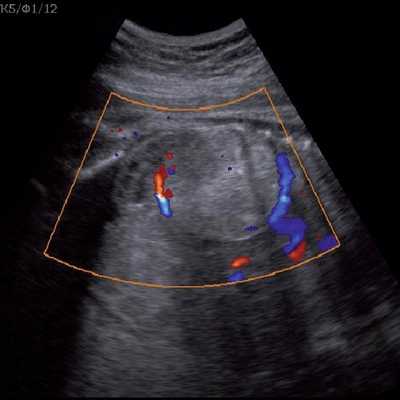

Под диафрагмой справа визуализировалось гиперэхогенное опухолевидное образование несколько неоднородной солидной структуры, с четкими ровными контурами, размером 50x38x35 мм. К нижнему полюсу данного образования прилежала правая почка, имеющая нормальные размеры, форму и структуру. Нижняя полая вена была смещена кпереди и влево. Обращала на себя внимание выраженная гепатомегалия, причем структура печени не была однородной. Она содержала множественные гиперэхогенные включения размерами до 17 мм, окруженные тонким гипоэхогенным периферическим ободком. Цветовое допплеровское картирование(ЦДК) демонстрировало интенсивную периферическую васкуляризацию опухоли (рис. 1-3).

Рис. 3. Метастазы в печени плода. Поперечное сечение брюшной полости плода. Гепатомегалия. В структуре печени плода определяются округлые включения несколько повышенной эхогенности (стрелки), с гипоэхогенным ободком - метастазы.